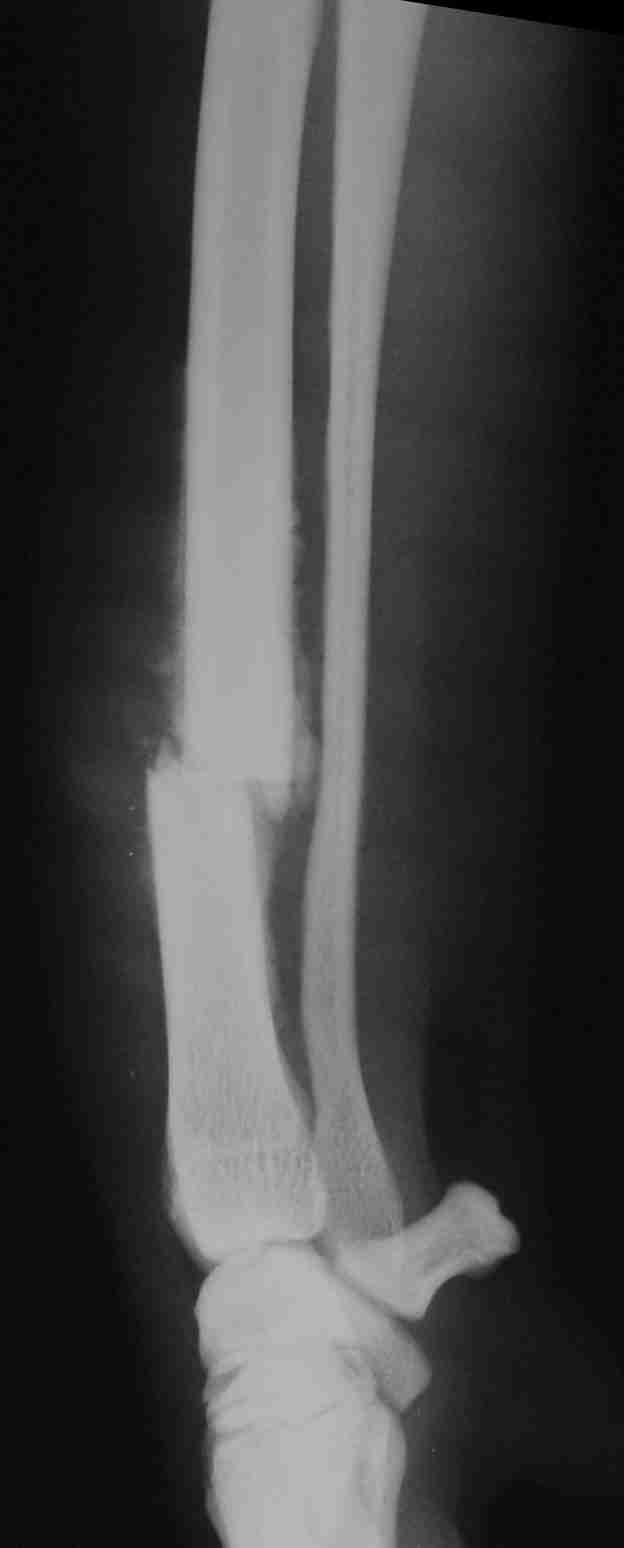

כלב שהגיע למרפאה עם תלונה של צליעה על רגל קדמית במשך מספר שבועות. בצילום הרנטגן ניתן לראות שעצם האמה נשברה והחל תהליך עצמי של קיבוע השבר ע"י רקמות הגוף – נראה כעננות בהירה סביב לאזור השבר. ייתכן שאם הכלב היה מגיע בזמן הפגיעה, ניתן היה לקבע את הרגל בצורה טובה יותר. נסיון לקבע את הרגל טוב יותר בשלב כזה – דורש שבירה מחודשת של העצם.